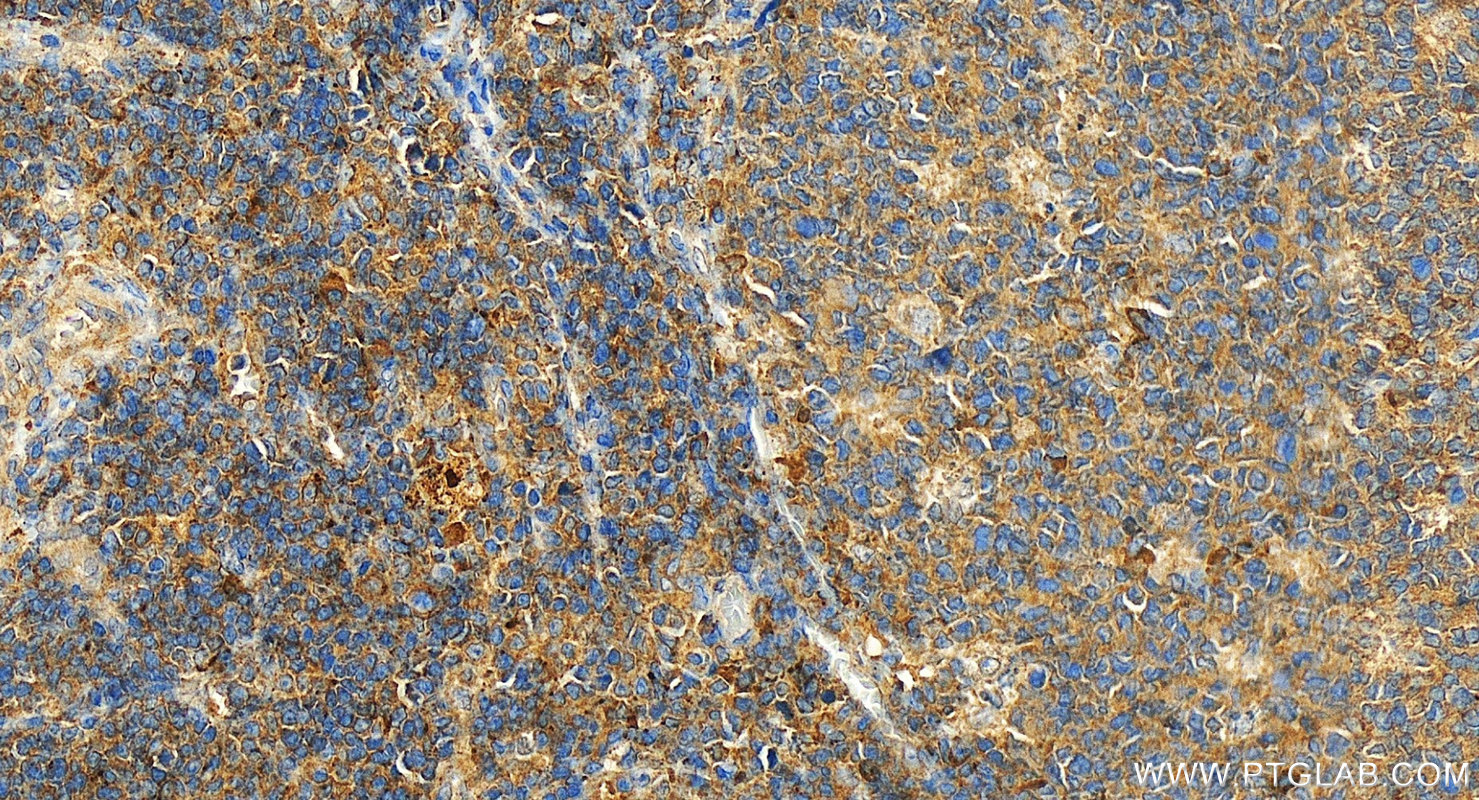

| Positive IHC detected in | human tonsillitis tissue Note: suggested antigen retrieval with TE buffer pH 9.0; (*) Alternatively, antigen retrieval may be performed with citrate buffer pH 6.0 |

| Immunohistochemistry (IHC) | IHC : 1:500-1:2000 |